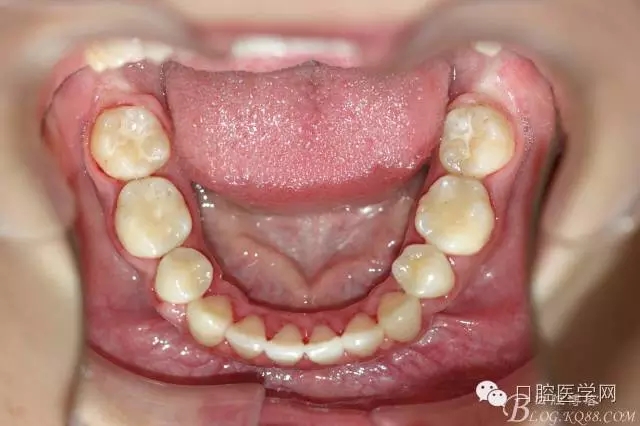

正畸前照片:

正畸查:替牙合。第一恒磨牙中性合。上牙弓尖圓型下牙弓方圓型。前牙覆合3度覆蓋7.5mm。下前牙咬到上舌側(cè)牙齦。上頜擁擠4.0mm,下頜擁擠

3.0mm。上頜稍前突下頜后縮,上下唇前突,上前牙覆蓋下唇,下唇外翻。面下三分之一過短,頦唇溝明顯,開唇露齒,頦饜窩明顯。顳下頜關(guān)節(jié)開閉口無彈響,無壓痛,開口型開口度正常。